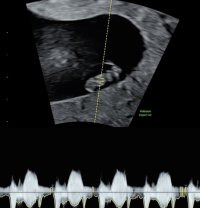

Foreløpig satt tilbake fra 6+4 til 6+2